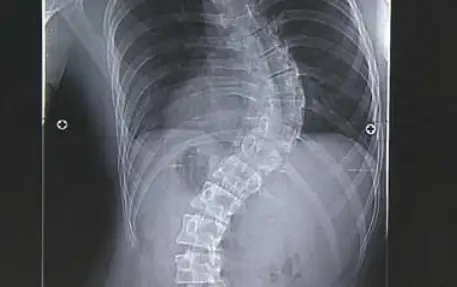

우리 몸의 척추는 아시다시피 휘어져 있습니다. 어느 정도의 굽은 상태이기 때문에 비정상은 아닙니다. 하지만 옆면이 아닌 정면에서 보았을 때 척추가 옆으로 휘어져 있다면 문제가 되며 이를 척추 변형이라고 합니다.

척추 측만증이란 바로 척추가 똑바로 서지 못하고 옆으로 휘어져 있는 상태를 말합니다. 단순하게 휘어져 있는 상태가 아니라 척추뼈가 회전이 되어 옆에서 보았을 때 3차원적인 변형을 말합니다. 그래서 심하게 되면 몸이 앞으로 굽어져 휘어지게 됩니다.

척추 측만증의 증상은 대체로 청소년기에 가장 흔하게 발생할 수 있으며 보통 척추 측만증 환자는 척추의 변형만을 호소하지만, 문제는 요통이 발생한다는 점입니다. 상체가 앞으로 확실히 기울어지며, 한쪽 어깨가 삐뚤어지게 되면서 한쪽 어깨뼈가 두드러지게 나옵니다.

심하면 갈비뼈가 변형이 되고 심장과 폐에 장애가 유발할 수 있습니다. 척추 측만증을 치료하지 않으면 폐가 줄어들어 폐부전이 오며, 허리통증과 허리디스크 및 신경통으로 진행하게 됩니다. 이렇게 된다는 질병에 의한 척추 측만증을 의심할 수도 있으므로 전문의의 진단을 받아보시는 것을 추천드립니다.